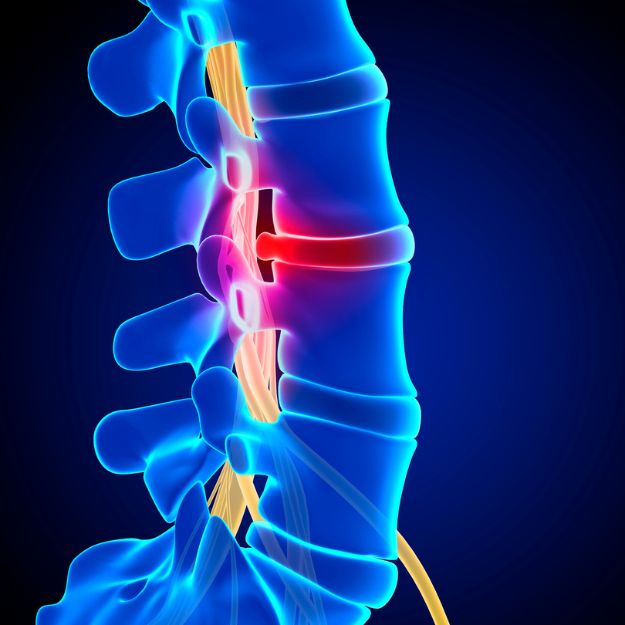

Cuidados para aliviar compressões nervosas e melhorar qualidade de vida.

Atuação em hérnia de disco, fraturas da coluna, escoliose, estenose vertebral e processos degenerativos.